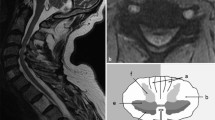

The introduction of MRI in the mid-1980s offered clinicians high-resolution anatomic images to facilitate clinical decision-making [8]. Conventional T1 and T2 sequences (along axial and sagittal planes) are typically employed for detailed visualization of the cervical spine anatomy. The normal cervical spinal cord travels through the lordotic spinal column, bounded anteriorly by vertebral bodies (VBs) and posterior longitudinal ligament (PLL), posteriorly by ligamentum flavum (LF) and lamina, and laterally by pedicles (Fig. 9.1). Kato et al. [37] described the normal morphology, age-related changes, and abnormal findings on MRI in 1211 asymptomatic patients to establish mean values for the cervical spinal canal, dural tube, and spinal cord. Spinal canal size is dependent on many factors, including spinal level, age (decreasing size with increasing age) [6, 37], gender [38], and underlying pathology (congenital stenosis or degenerative changes) [37].

As the extent of spinal cord damage increases, the water content increases; this affects changes to tissue relaxation, which equates to changes on T1 and T2 sequences. With more water content, tissue exhibits hypointensity on T1 and hyperintensity on T2. Overall, as T2 is more sensitive to variation in water content than T1, changes on T2 are frequently observed prior to changes on T1. DCM patients frequently demonstrate T2 hyperintensity and, less commonly, T1 hypointensity, at the level of compression [6]. Both features are helpful diagnostic findings [6]. In particular, T2 hyperintensity can be present in up to 85% of patients with DCM [6]. Moreover, the extent of T2 hyperintensity (including size of signal change, relative intensity of signal change, and pattern of signal change) has been linked to clinical impairment in DCM patients [51]. On the other hand, T1 hypointensity, which can indicate cavitation and disruption of fiber tracts, may be a specific feature for poorer baseline neurological function and worse surgical results [52,53,54]. Snake-eye appearance, where symmetric hyperintensity of the spinal cord is observed on axial T2 sequences, is a rare finding. Through autopsy studies, this imaging feature has been associated with cystic necrosis due to mechanical compression and venous infarction, corresponding to damage of gray matter and neuronal loss in the anterior horn [55]. Not surprisingly, snake-eye appearance has been considered a poor prognostic factor for surgical outcome [55].